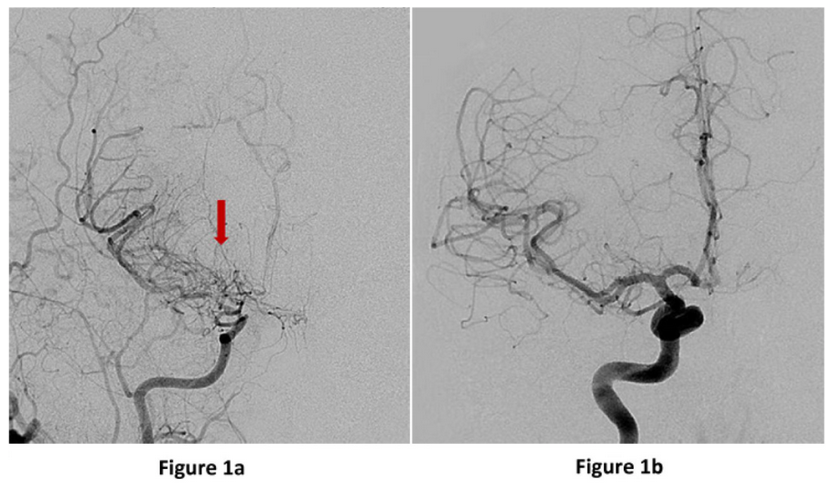

Figure 1. Moyamoya disease

Figure 2: Anterior or front view (image on the left) of a brain angiogram showing the right internal carotid artery narrowing into the small tangles of moyamoya “puff of smoke” vessels (red arrow). An anterior view of the right internal carotid artery cerebral angiogram showing a normal branching pattern for comparison (left).